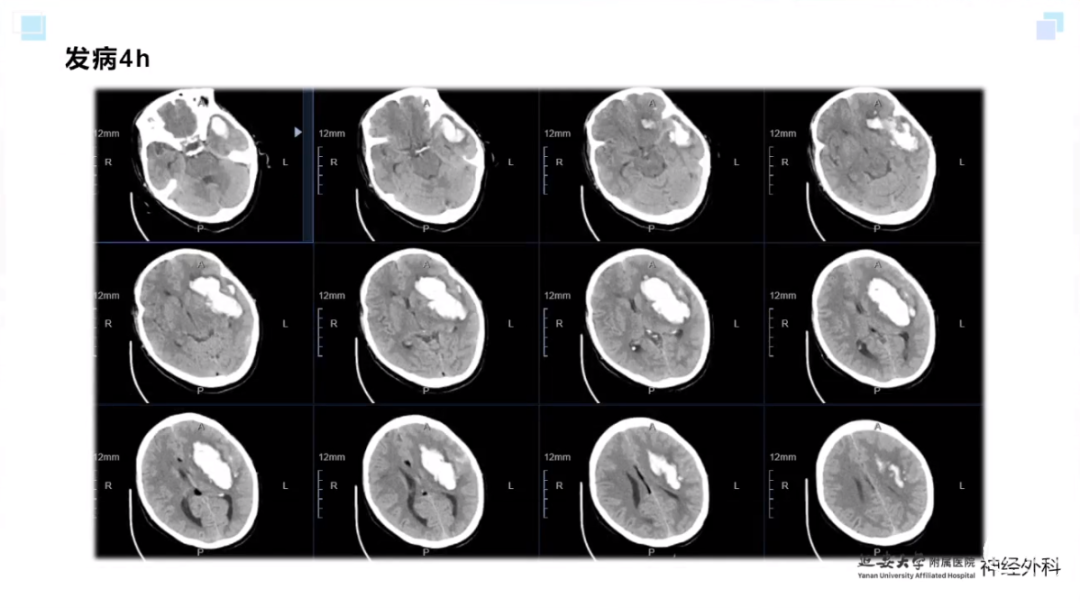

今天为大家分享的是《监测有道丨颅脑创伤-神经重症周刊》第337期,由延安大学附属医院神经外科贾云峰主任医师带来的:神经内镜为主导的多术式组合在重症脑出血中的应用,欢迎阅读、分享。

长期从事神经外科疾病的基础与临床研究。专长于神经急危重症综合治疗、神经内镜脑出血微创手术、脊髓脊柱疾病显微外科微创治疗、颅内及脊髓肿瘤、脑血管病、脑、脊髓先天畸形的微创治疗。参与主持完成科研项目《尼莫地平对脊髓损伤的作用研究》等,获陕西省自然科学优秀论文奖。参与国家卫健委牵头的《自发性脑出血的多中心登记研究》等项目研究及《脑出血患者颅内压监测》《脑出血后脑水肿的治疗》专家共识的制定。以第一作者在国内外发表核心期刊20余篇,SCI收录文章1篇,多次应邀在中华医学会、中国医师协会全国神经外科学年会交流发言。主编及参编著作3部,国家发明专利2项